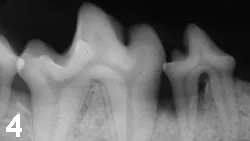

Local tissue may appear normal despite underlying disease, defining the need for periodontal probing and radiography (Figures 3-5).

Figure 4: Radiograph of the right mandible of the patient in Figure 3. Bone loss is evident surrounding the roots of the fourth premolar. The patient was observably more active after surgery to correct the defect.

Figure 5: Surgical exposure of a defect in a patient similar to that in Figures 3 and 4. Granulation tissue is seen occupying the void created by periodontal bone loss (arrow).